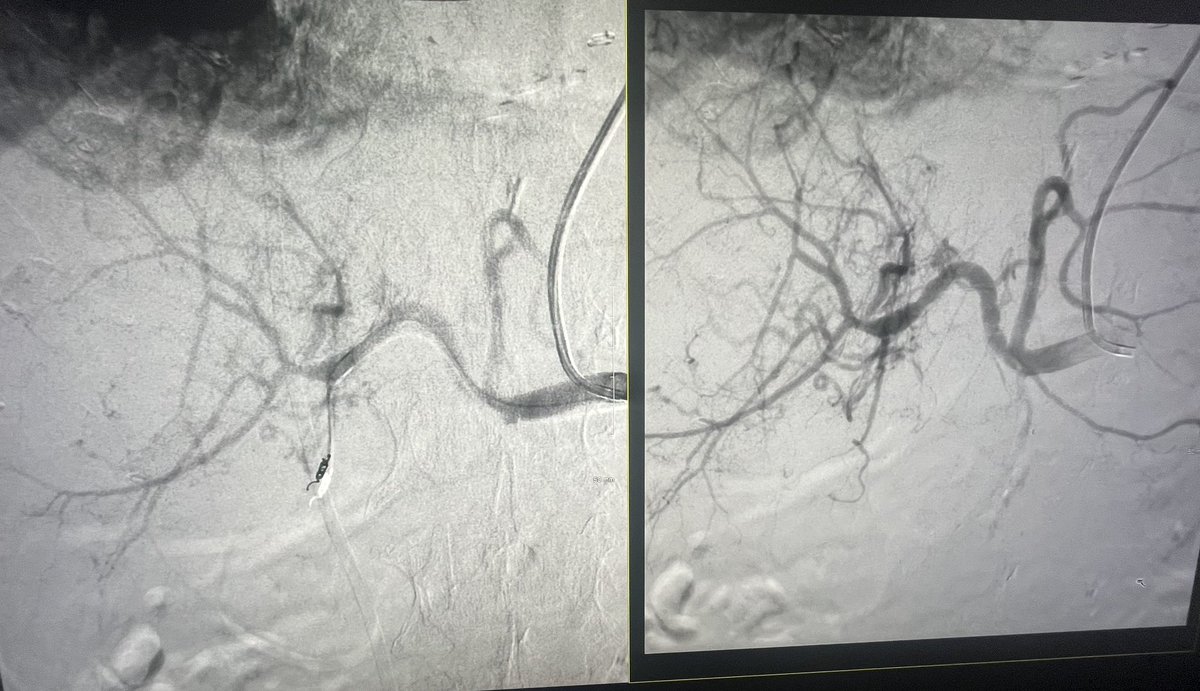

@SDhandMD @ChengaziMD @smbracewell @t_intheleadcoat @saherssabri @kmadass @drochohan @IR_Doctor @IRKhalsa @laronecampbell @drvarshana @drcostantino1 @MoonJustaniah @theblanketdog @JuliusChapiro @linemonkeymd This was a fun one! Finally got the drain out after a little glue embo